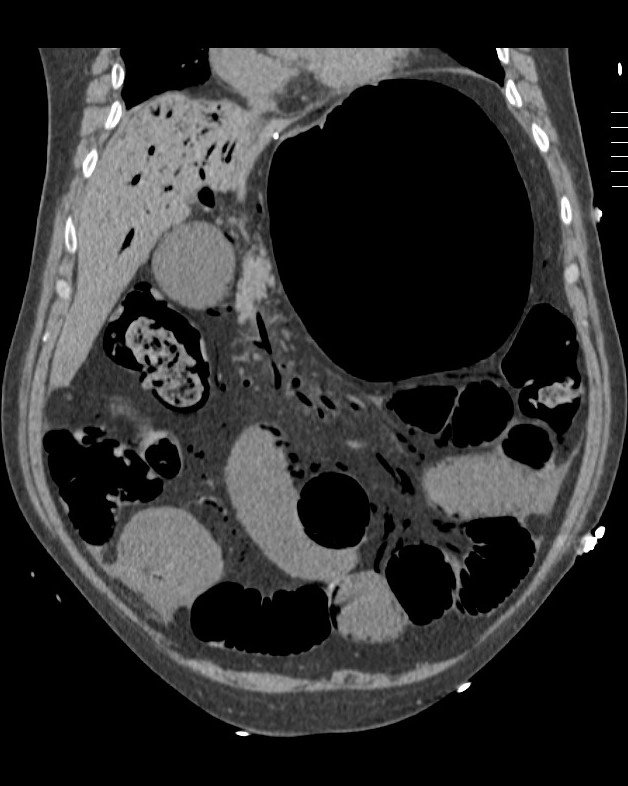

• Tăng áp lực tĩnh mạch cửa (Portal Hypertension)

• Thay đổi đậm độ gan thoáng qua trên CT (Transient hepatic attenuation differences - THADs)

• Tắc nghẽn gan thụ động (Passive hepatic congestion)

• Hội chứng Budd-Chiari (Budd-Chiari syndrome)